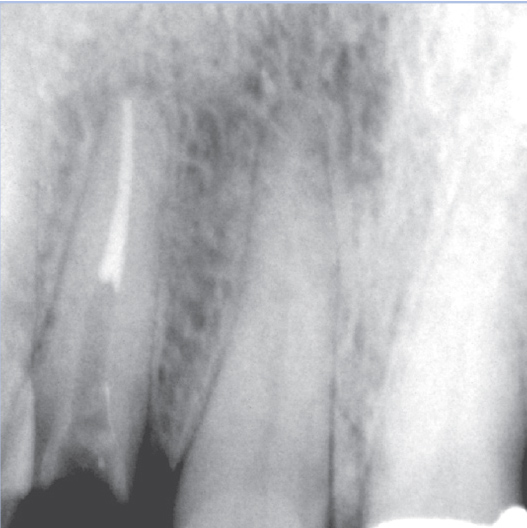

Before

After

Before Root Canal treatment

After Root Canal treatment